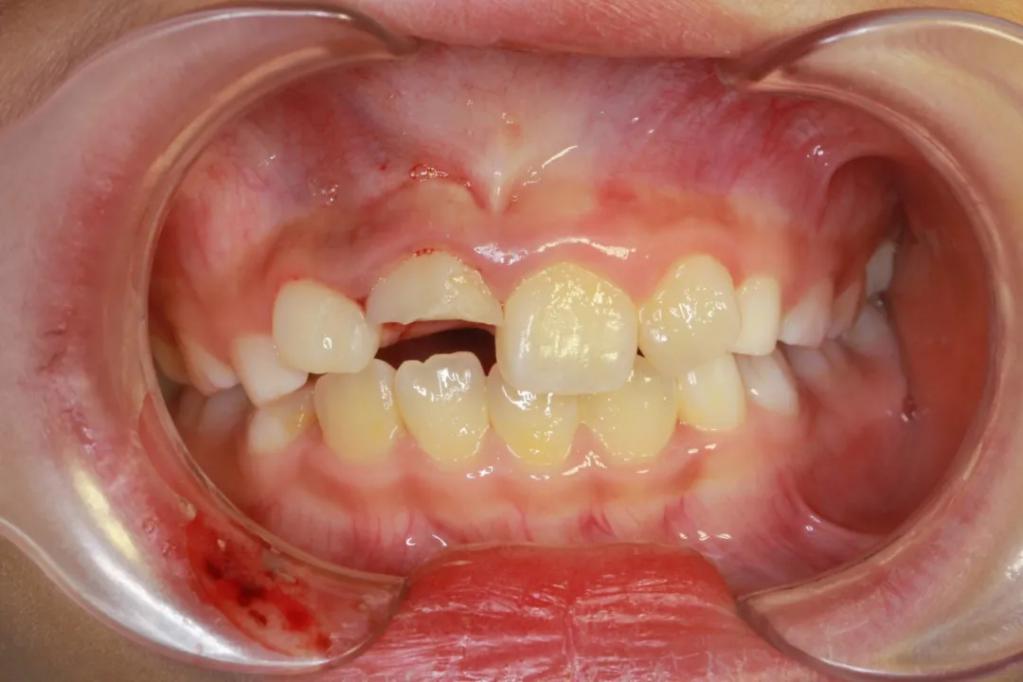

治疗前

昨天上午11时左右,8岁的小女孩甜甜(化名)在小区中骑自行车,由于刹车太急摔倒造成门牙断裂,嘴唇也流血了,这可把爸爸妈妈吓坏了,赶紧带甜甜来看口腔急诊。

接诊的儿童口腔科医生张丽文为了甜甜做了详细的检查,与急诊医疗组组长王莹医生会诊评估了甜甜的状况之后,考虑立即进行消毒清创,并且给暴露的牙髓作活髓切断的治疗,即切除暴露受伤感染的牙神经,保护根方牙神经。

牙外伤的第二步处理断冠再接,考虑甜甜的前牙有点拥挤,如不及时处理两边的牙齿移位侵占断牙的空间,接断冠就困难了。因此,张丽文医生和急诊团队又开始了忙碌的断冠再接。年轻恒牙的活髓切断和断冠再接是很精细的治疗,从准备工作到结束,相当的耗时。等甜甜完成治疗,时间已经到了下午14时多。